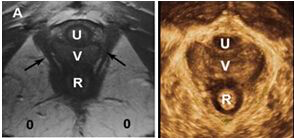

随着超声技术的不断更新换代,超声探头能够获取盆底所需的结构和运动信息,通过三维/四维重建功能,对获取数据进行图像还原处理,可以获得媲美MRI成像的立体图像。如下图所示。